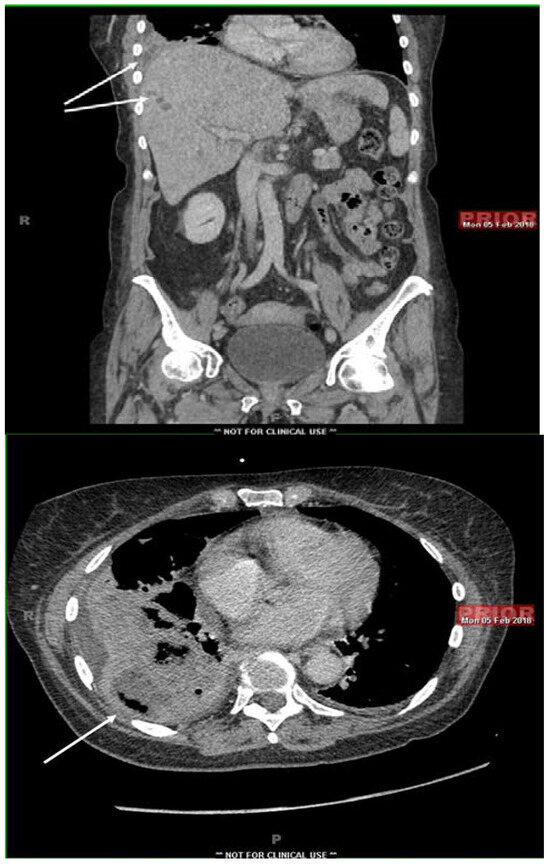

Introduction: Fusobacterium nucleatum is a Gram-negative, obligate anaerobic bacterium which predominantly resides within the oral cavity and causes acute abscesses and venous thrombosis, primarily in the head and neck region, but could have unique clinical presentations in different anatomical regions of the body. Case report: We present a case of subacute liver abscesses extending to the lung. The histopathological examination showed extensive necrosis and fibrosis. The chronic course, extensive fibrosis and extension across the anatomic barriers were suggestive of actinomycosis. two sets of blood cultures grew Fusobacterium nucleatum, only 16s rRNA analysis of the liver tissue and pleural fluid revealed F. nucleatum DNA without other organisms. The clinical and pathological features of our case illustrate that F. nucleatum may mimic actinomycosis. Conclusions: This case illustrates that F. nucleatum should be considered in patients with subacute infections with extensive fibrosis that crosses anatomic barriers, mimicking actinomycosis. Full article